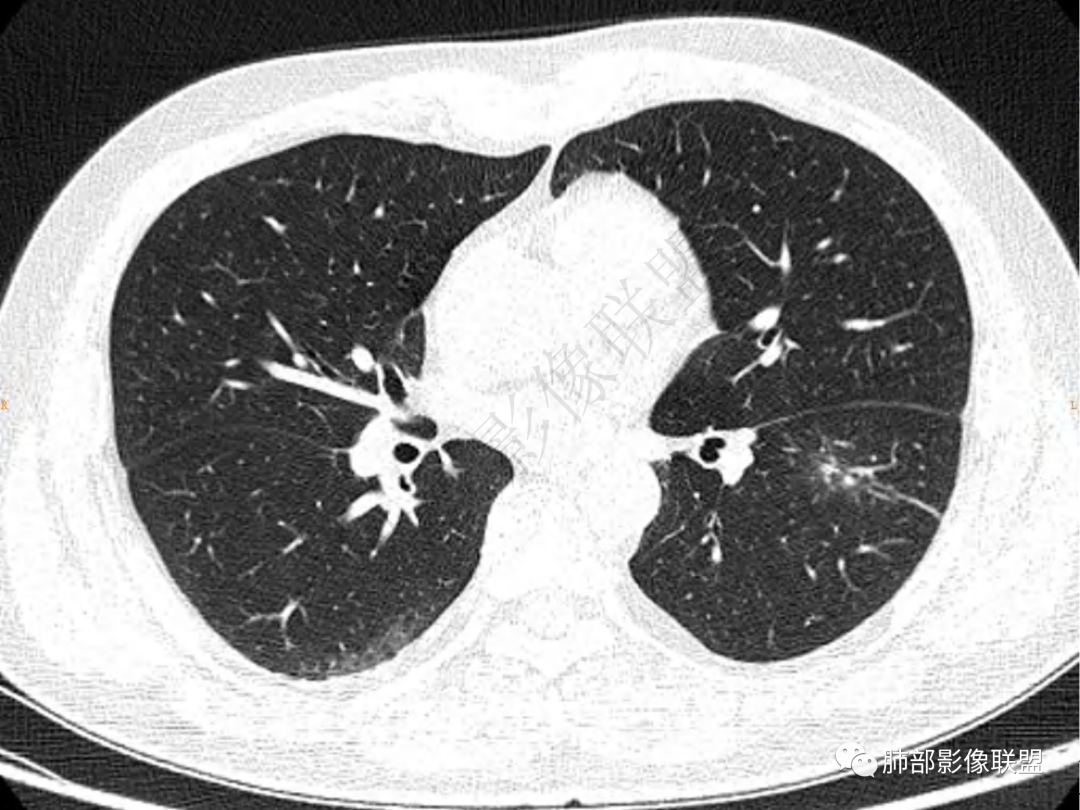

2.左肺下叶团片影,跨背段及内前基底段,实性部分类椭圆形,密度不甚均匀,可见毛刺及棘状突起,未见典型分叶及胸膜凹陷。病灶上下缘可见相应肺段支气管旁进侧出,管壁轻度增厚,未见狭窄阻塞。

3.周边较大范围磨玻璃影,边界相当模糊,小叶增厚明显。注意叶裂另一侧、左肺舌段亦可见磨玻璃影及增厚的小叶间隔。未见明确卫星病灶。

4.实性部分不均匀环形强化并显示一小范围低密度坏死区或空洞。较之肺窗,整体纵隔窗范围较小,提示病灶并不十分密实。抑或为不同时段图像。

1.病灶不够密实,没有典型分叶,收缩乏力等,支气管未见截断等,缺乏一般肿瘤性肿块特征。

2.周围磨玻璃影边界不清缺乏限制,甚至“激惹”到相邻肺叶,也许提示较明显的炎性水肿。

正如多数老师分析到的,本例病灶炎性特点比较明显。